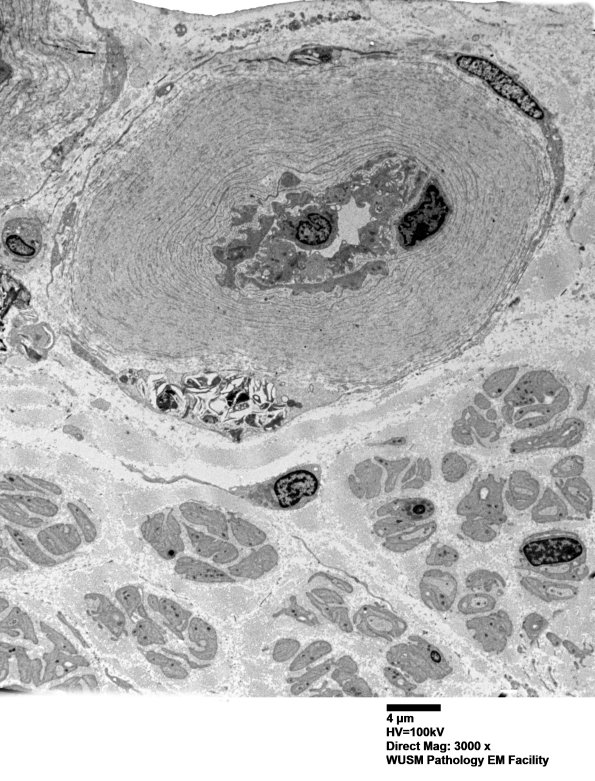

6C1-3 Thickening of this vessel wall consists of accumulated basal lamina fragments (arrowheads, 6C3) and collagen. (electron micrographs)